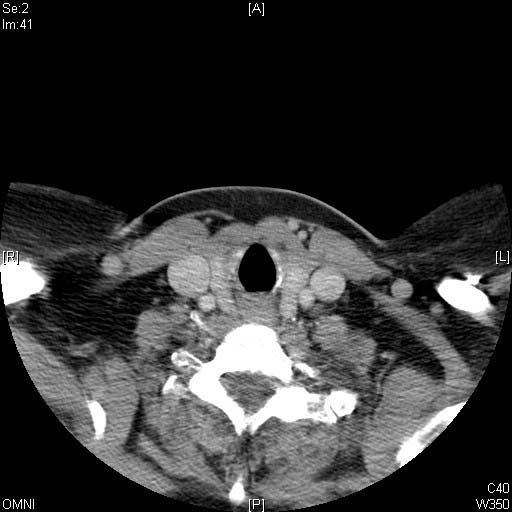

Identify Thyroid cartilage, Trachea and Esophagus